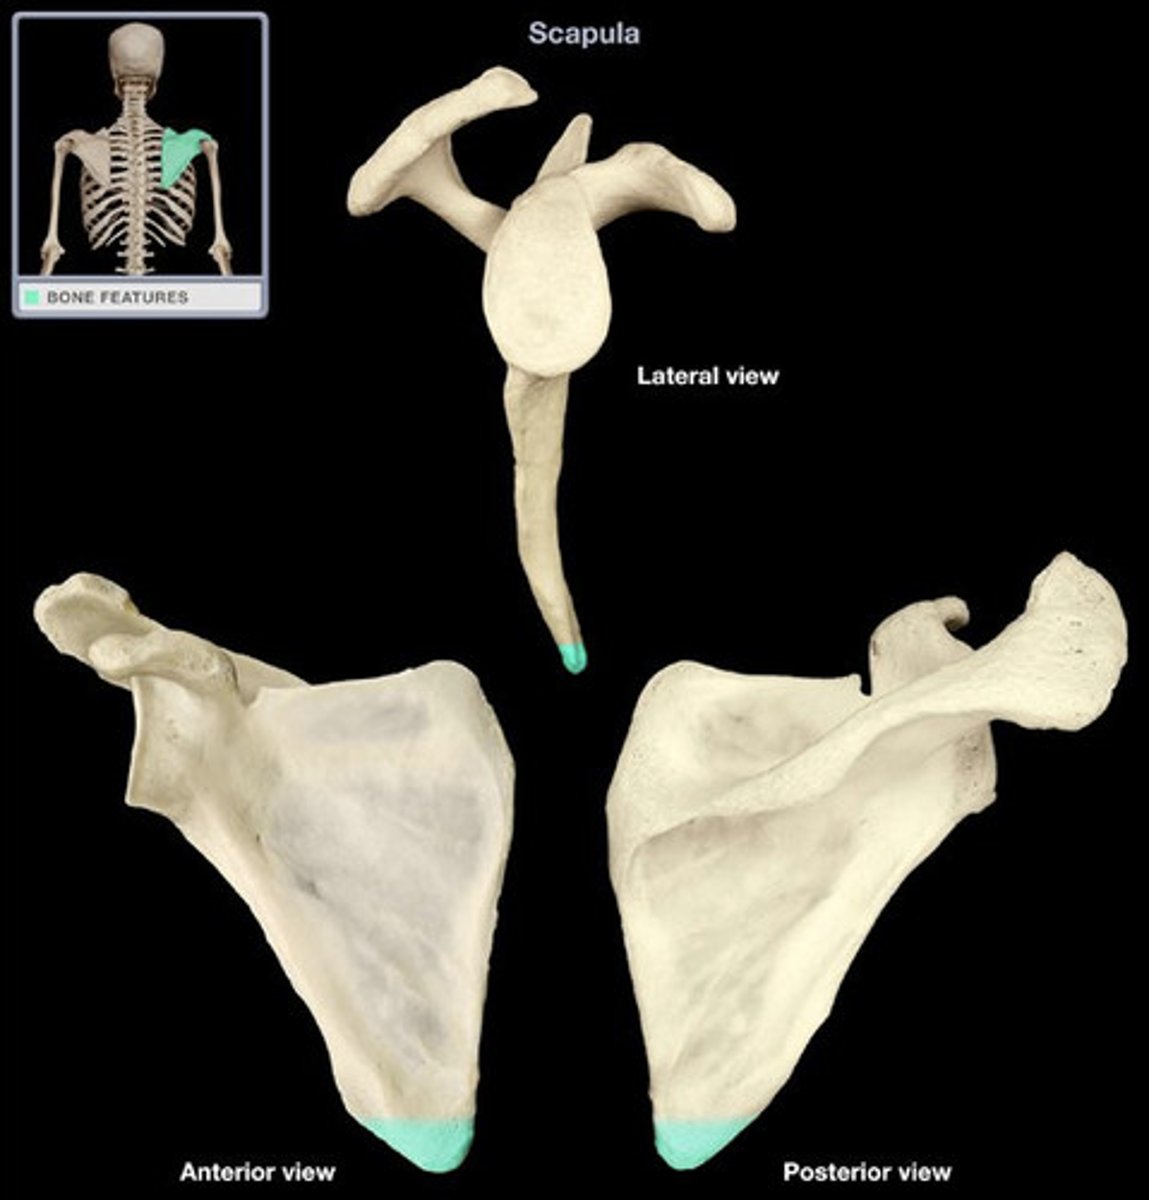

Describe the scapula:

triangular bone

Location of the scapula:

posterior part of the thorax, overlying the 2nd-7th ribs

Scapula articulates with:

humerus (joint) and thoracic wall (physiological scapula-thoracic joint)

Surfaces of the scapula:

- posterior (convex)

- costal (concave)

- lateral

What structures are on the posterior surface of the scapula?

- spine of scapula

- acromion

- supraspinous fossa

- infraspinous fossa

What structure is on the costal surface of the scapula?

subscapular fossa

What structures are on the lateral surface of the scapula?

- glenoid cavity

- coracoid process

- head of scapula

- neck of scapula

- suprascapular notch

Coracoid process of scapula:

- on lateral surface of the scapula

- superior to the glenoid cavity, projects anterolaterally

What are the angles of the scapula?

- superior

- inferior

- lateral

Where is the superior angle of the scapula?

angle at the union of superior and medial borders

Where is the inferior angle of the scapula?

angle at the union of medial and lateral borders

Where is the lateral angle of the scapula?

angle contains the head of the scapula